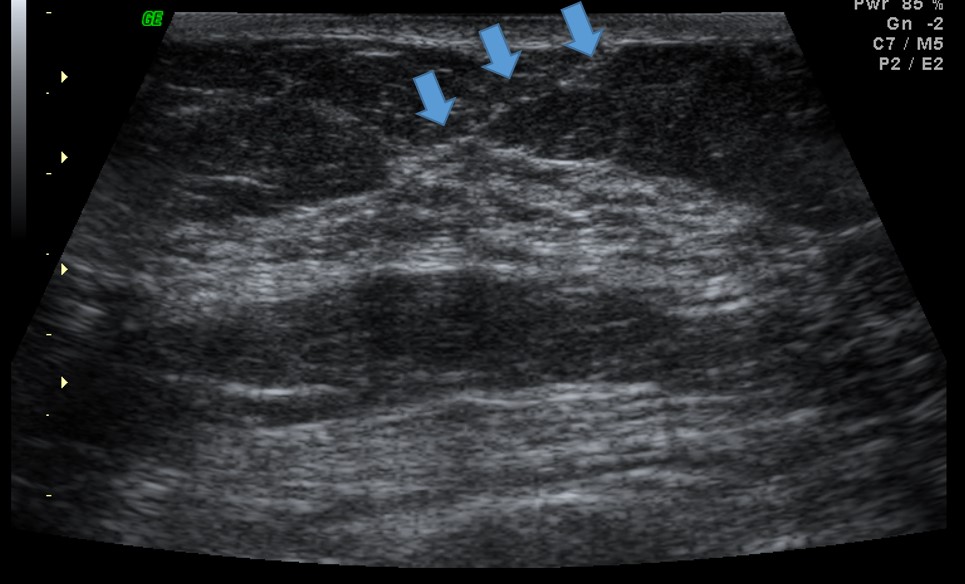

Da superfície para a profundidade, identificam-se: a pele ecogênica; a gordura subcutânea ou pré-glandular, geralmente isoecóica e atravessada pelos ligamentos de Cooper; a zona fibroglandular, de ecogenicidade predominantemente aumentada; e a gordura retroglandular, novamente isoecóica. Todo esse conjunto repousa sobre o músculo peitoral maior, cuja ecogenicidade é semelhante à da gordura. Além das próprias camadas, as interfaces entre elas — como as fáscias pré- e pós-glandulares — constituem marcos anatômicos importantes para a localização das lesões mamárias. O reconhecimento sistemático dessas camadas e de seus limites é essencial para a correta interpretação dos achados ultrassonográficos e para uma comunicação mais precisa da localização das lesões.

A maior parte dos ductos e das unidades funcionais da mama, incluindo as unidades ducto-lobulares terminais (TDLUs), localiza-se na zona glandular, também denominada zona mamária. Essa região é delimitada anteriormente pela fáscia pré-glandular e posteriormente pela fáscia pós-glandular, que definem seus limites anatômicos à ultrassonografia.

A fáscia pré-mamária atua como uma barreira anatômica relativa à progressão superficial das lesões originadas na zona glandular. Como consequência, muitas lesões tendem a crescer preferencialmente no sentido ântero-posterior, ultrapassando planos teciduais, em vez de se expandirem paralelamente à pele. Esse comportamento anatômico explica, em parte, o padrão “taller-than-wide”, considerado um critério morfológico suspeito na ultrassonografia mamária.